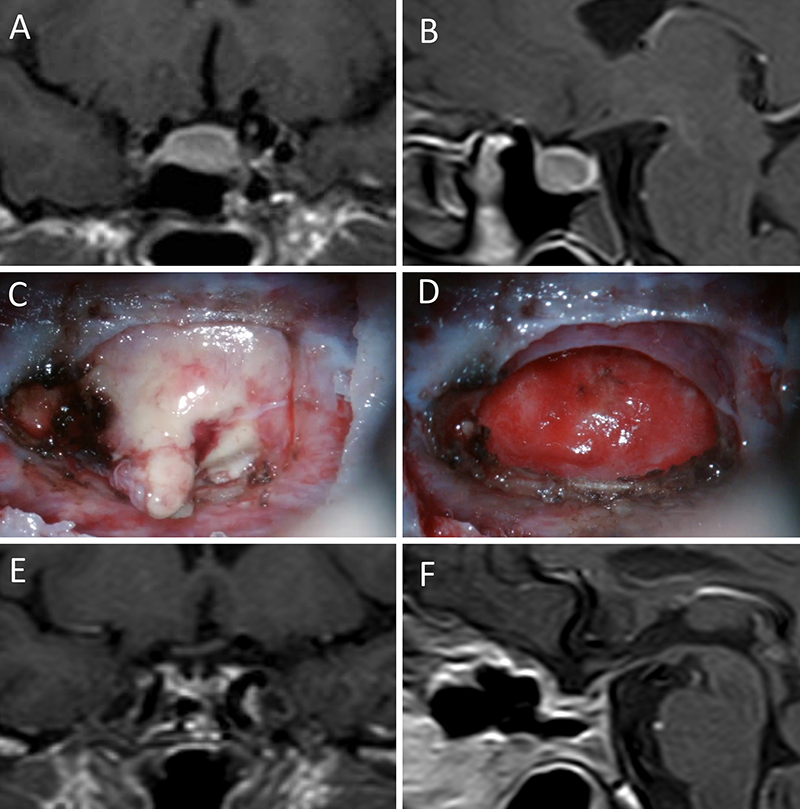

Figura 1: Macroadenoma no funcionante en mujer de 65 año s. Se decidió la cirugía tras evidenciarse crecimiento en los controles. Evolucionó favorablemente desde el punto de vista clínico-radiológico. A-B: RM preoperatoria; C-D: intraoperatorio; E-F: RM postoperatoria.